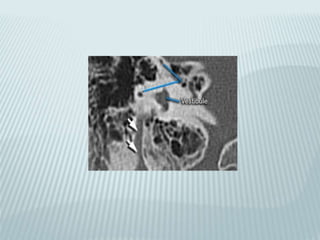

VESTIBULAR AQUEDUCT

 10 mm long endolymphatic duct

 From common crus to post wall of petrous

pyramid

 Joins endolymphatic sac nestled in leaves of

dura

 Equilibration of endolymphatic fluid pressure

 subdural

COCHLEAR AQUEDUCT

 8 mm long perilymphatic aqueduct

 From basal turn of cochlea to medial border

of jugular foramen

 Regulation of CSF and perilymphatic fluid

pressure

 Subarachnoid